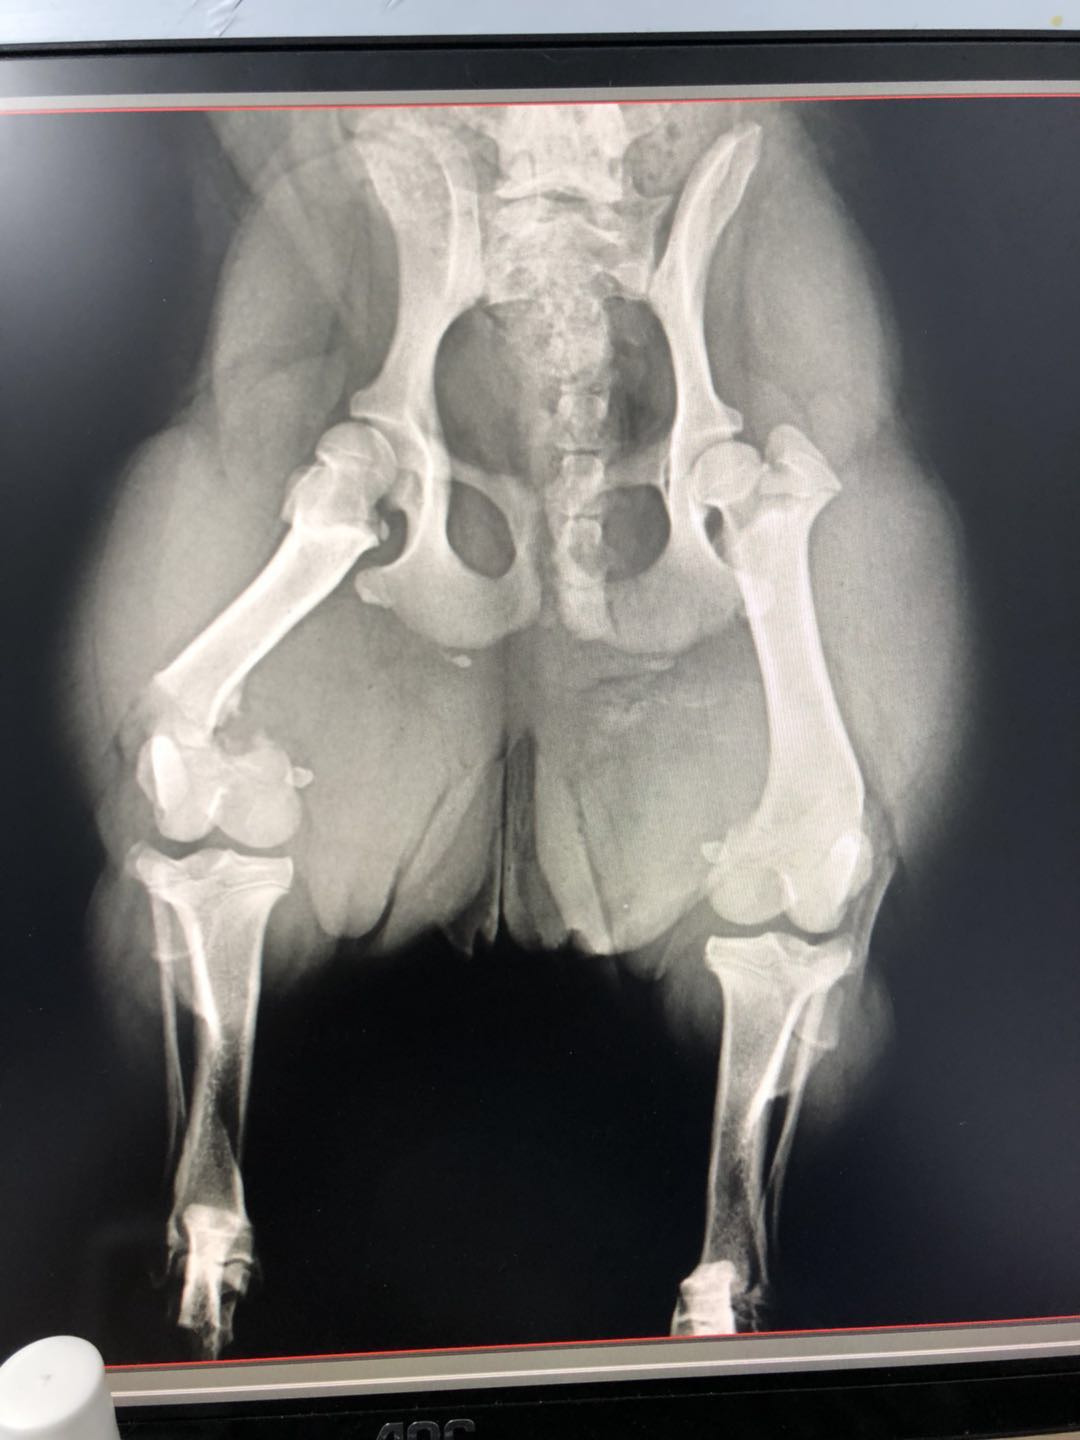

骨折完美复位的小柯基,医生们技术真到位